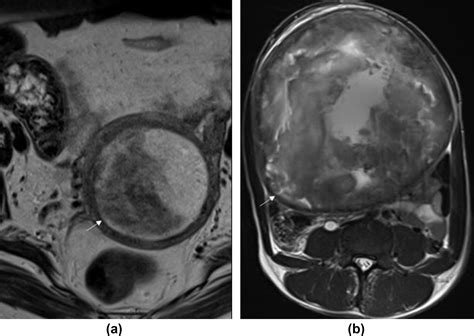

Diagnosing uterine myoma degeneration involves a combination of medical history, physical examination, and imaging tests. The diagnostic process typically includes:

• Imaging Tests: Ultrasound, MRI, or CT scans to visualize the fibroids and assess the extent of degeneration.